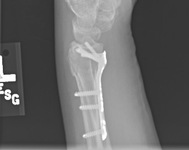

Fixação com placa, após redução aberta, com placa e parafusos colocados em posição volar

Do acervo do Dr. Chaitanya S. Mudgal